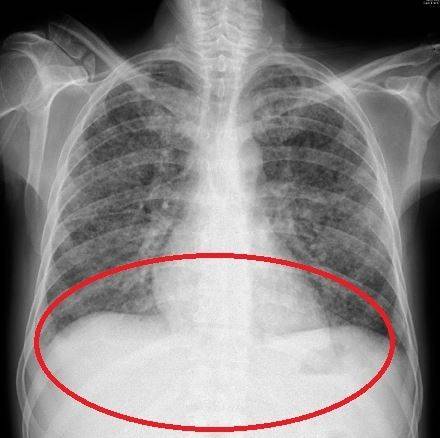

정밀 검사 결과 환자의 폐와 대변 검체에서 분선충이 검출됐다. 회충의 한 종류인 분선충은 피부를 뚫고 체내로 침투해 복통이나 발진 등을 일으킨다. 주로 맨발로 흙을 밟을 때 토양 속에 서식하던 유충이 피부를 통해 몸 안으로 유입되며, 면역 기능이 떨어진 사람에게는 치명적인 결과를 초래할 수 있다.

의료진은 “남성은 알코올 중독과 당뇨병 등을 앓으며 면역력이 떨어진 상태에서 기생충에 과감염됐다”며 “이는 전신으로 기생충이 퍼져 생명을 위협하는 상황”이라고 설명했다. A씨는 과감염 판정을 받은 뒤 구충제인 이버멕틴을 투여받았으나, 치료 과정에서 패혈증과 폐출혈이 겹치며 끝내 사망했다.